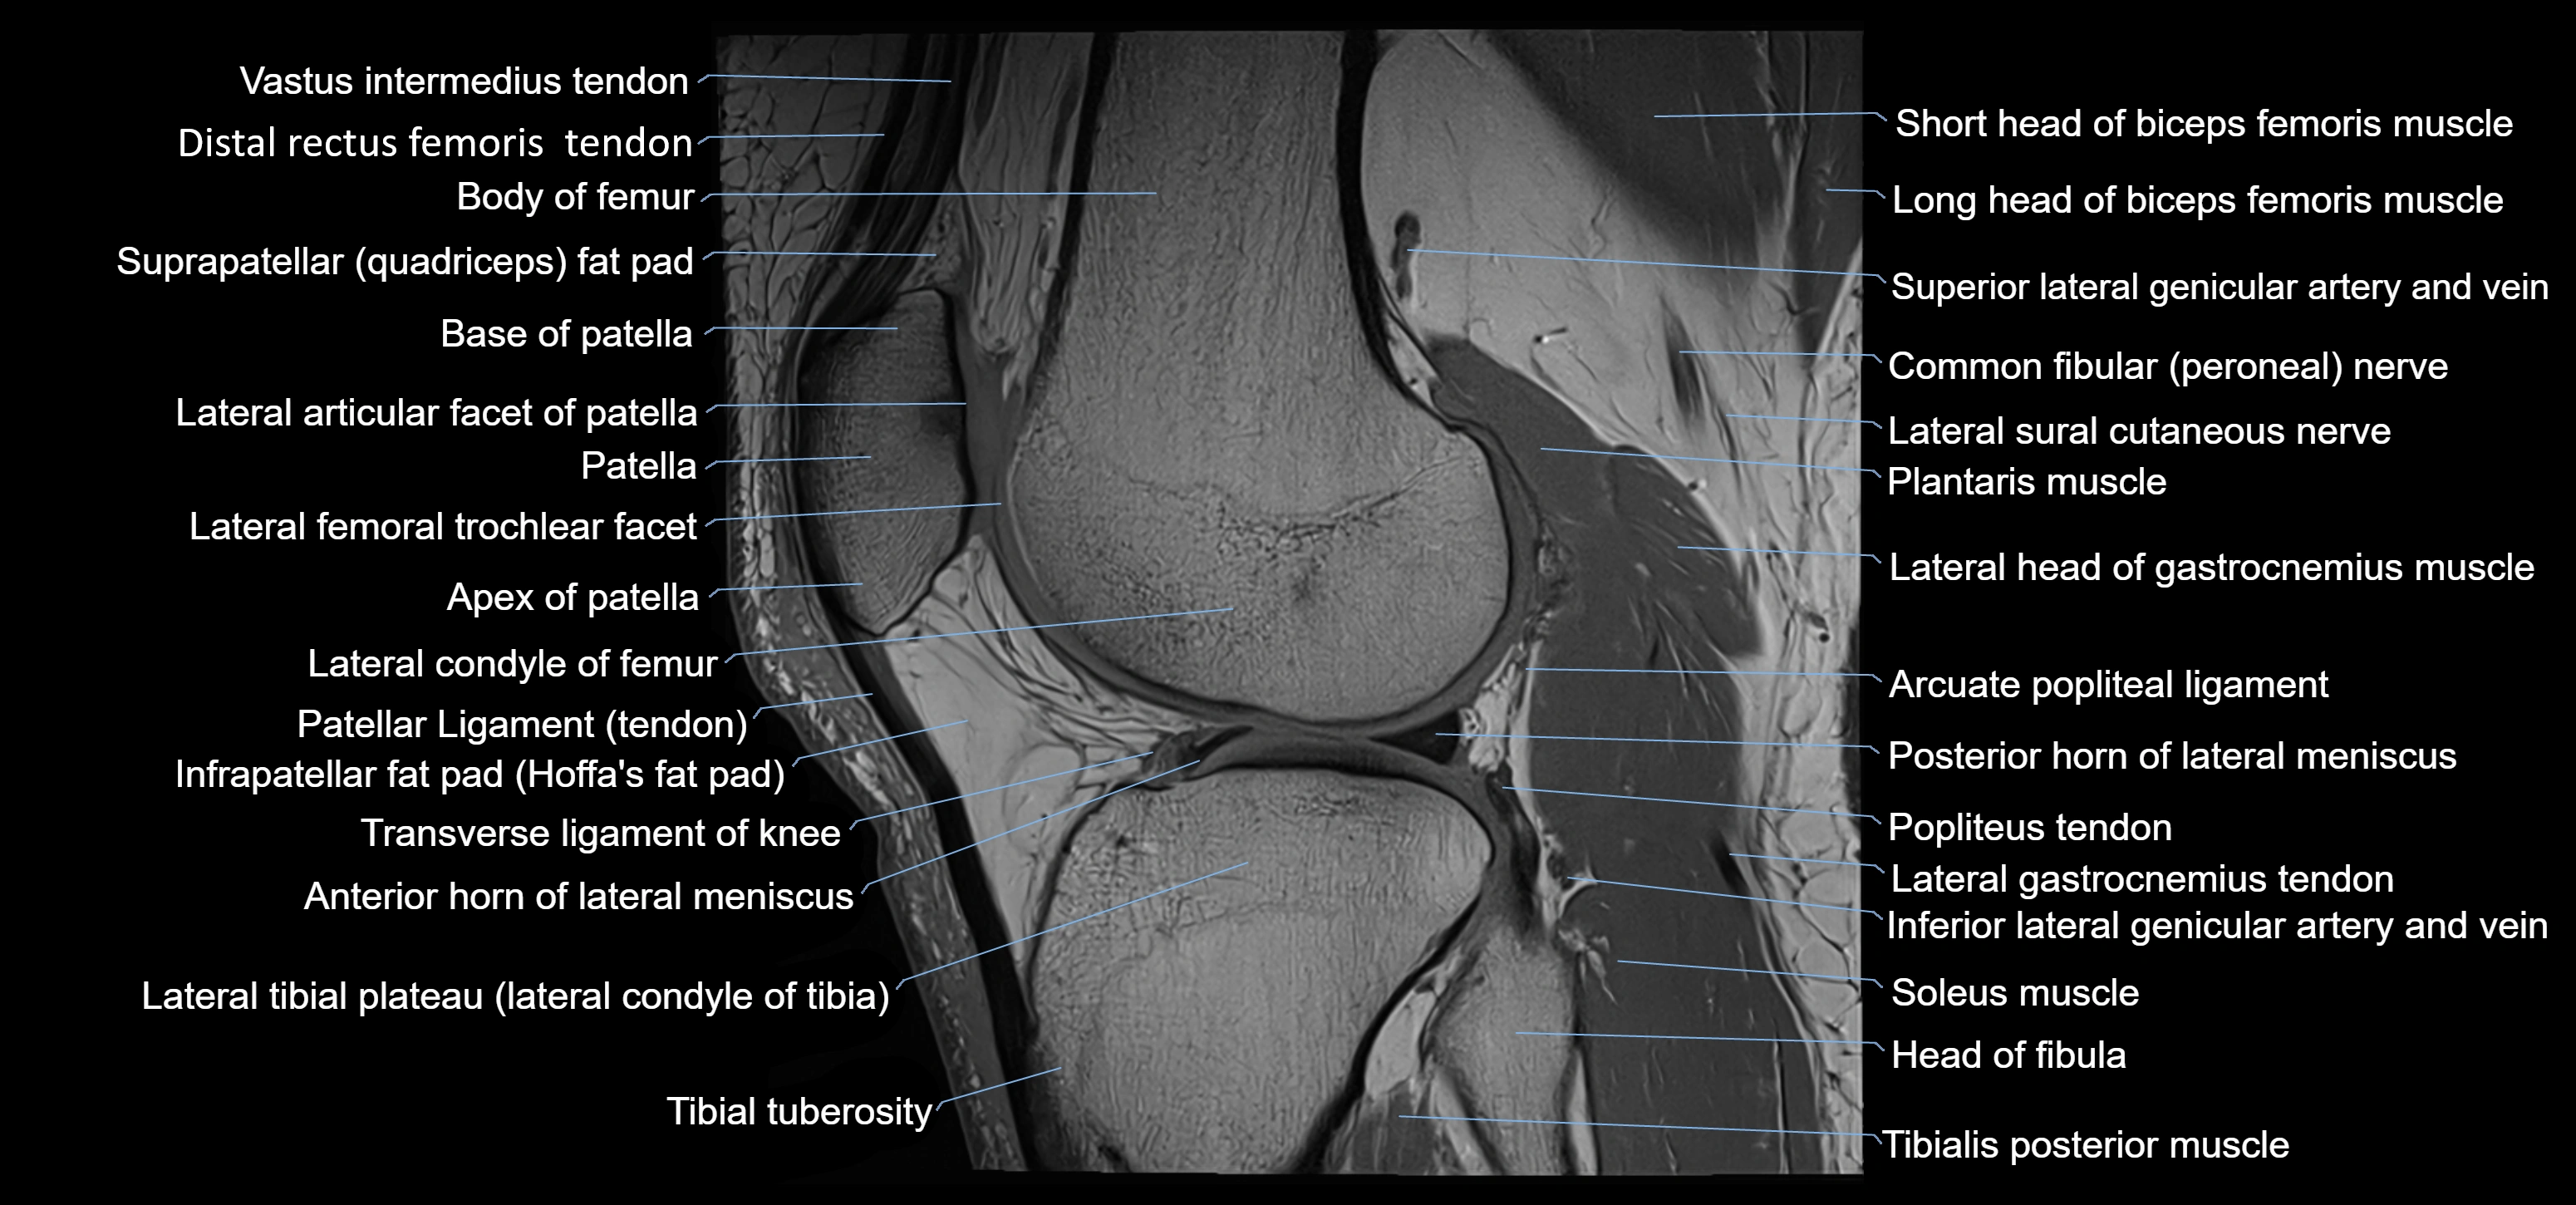

- Anterior horn of lateral meniscus

- Arcuate popliteal ligament

- Base of patella

- Biceps femoris muscle (Short head)

- Body of femur

- Distal rectus femoris tendon

- Distal vastus intermedius tendon

- Fibularis longus muscle (peroneus longus muscle)

- Head of fibula

- Inferior lateral genicular artery

- Inferior lateral genicular vein

- Infrapatellar fat pad

- Lateral articular facet of patella

- Lateral condyle of femur

- Lateral condyle of tibia

- Lateral gastrocnemius tendon

- Lateral head of gastrocnemius muscle

- Neck of fibula

- Patellar tendon (patellar ligament)

- Plantaris muscle

- Popliteus tendon

- Posterior horn of lateral meniscus

- Soleus muscle

- Superior lateral genicular artery

- Superior lateral genicular vein

- Suprapatellar fat pad

- Tibial tuberosity

- Tibialis anterior muscle

- Transverse ligament of knee